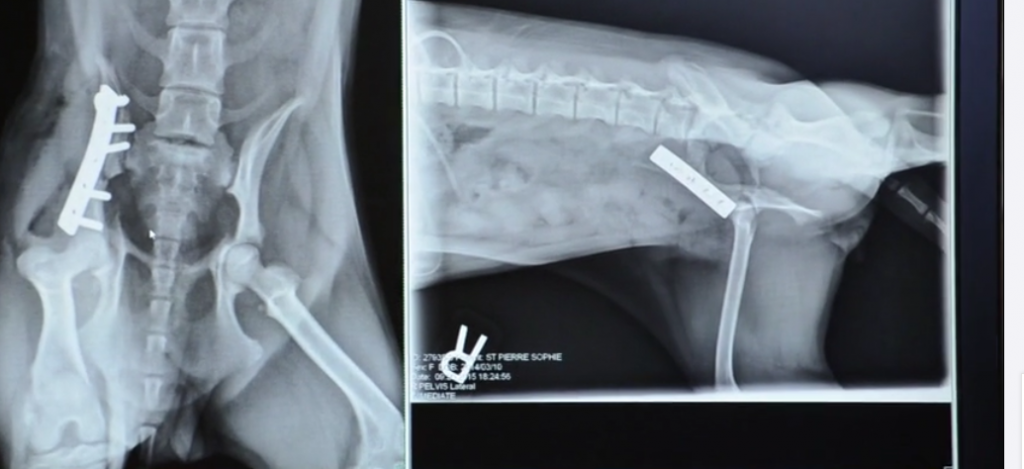

The terrier immediately went under a pelvis operation and it was a grand success. Within a week’s time the small terrier was not only able to walk properly but was also able run on its own feet which was a blissful experience.